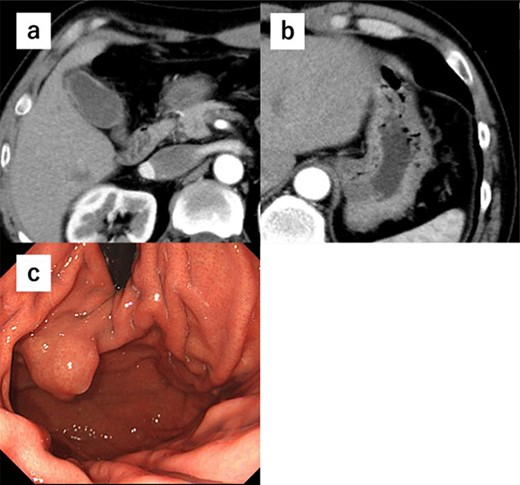

A 52-year-old man was diagnosed with acute cholecystitis after presenting to the emergency department of our hospital with right upper quadrant abdominal pain. Blood tests revealed the following measurements: white blood cell count, 15 300/mm3; C-reactive protein, 0.03 mg/dL; total bilirubin, 1.2 mg/dL; direct bilirubin, 0.7 mg/dL; alkaline phosphatase, 338 U/L; aspartate transaminase, 126 U/L and alanine aminotransferase, 66 U/L. The abovementioned values revealed an inflammatory reaction and mild elevation of hepatobiliary enzymes. CT revealed cholecystitis, and a submucosal tumor measuring 3.5 cm in diameter was incidentally detected (Fig. 4a and b). The patient was treated with antibiotics for cholecystitis and referred to our department for simultaneous surgery. Upper endoscopy revealed a tumor in the anterior wall of the gastric cardia near the EGJ (Fig. 4c). He underwent robot-assisted laparoscopic resection for the tumor, combined with endoscopy and robot-assisted cholecystectomy (Fig. 5a–c). The port positions were the same as those in Case 1. The operative time was 228 min, and blood loss was 1 mL. No adverse postoperative events occurred, and the patient was discharged on postoperative day 7.

(a) CT shows cholecystitis, and no gall bladder is found. (b) CT shows cholecystitis, and no gall bladder was found. A submucosal tumor measuring 3.5 cm in diameter was incidentally detected. (c) Upper endoscopy reveals the tumor in the anterior wall of the gastric cardia near the EGJ.